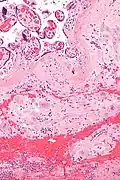

Micrograph of a chronic deciduitis, showing the characteristic plasma cells. H&E stain. |

Chronic deciduitis is a type of long-lasting inflammation that arises in pregnancy and affects the endometrial stromal tissue (decidua).

It is associated with preterm labour.[1] The diagnosis rests primarily on the presence of plasma cells.[2]